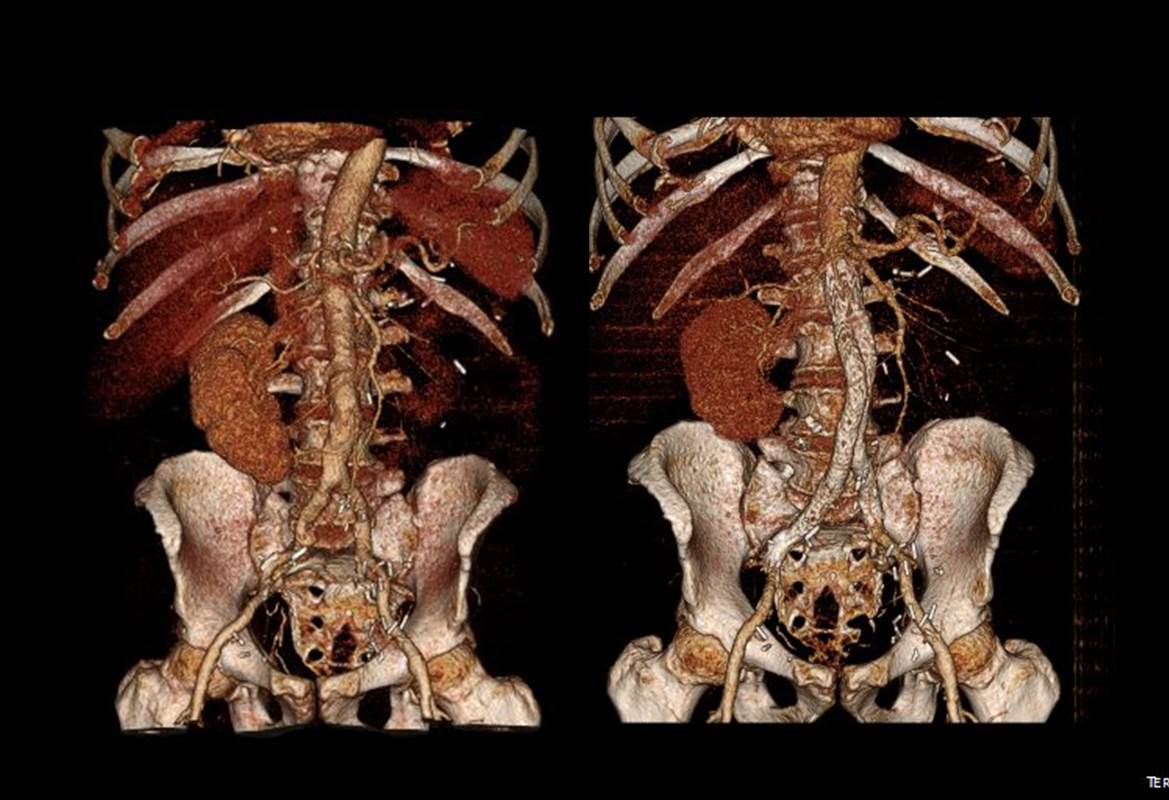

The patient is an active man in his 60’s with a history of hypertension who had known about a right common iliac artery aneurysm for several years and had come for an opinion. He was asymptomatic of pain. He had a prior splenic artery aneurysm embolization about a decade prior to presentation.. CT scan showed a large eccentric aneurysm arising from a retrograde chronic dissection dilating the right common iliac artery to over 4cm. This is typically iatrogenic, but impossible to know for sure. The left common iliac artery was ectatic to 2cm as was the aorta to 3 cm and all were “wavy.” This sort of tortuosity is the result of remodeling in the axis of flow resulting in lengthening of the artery and is found in those with the substrate for aneurysmal degeneration (footnote). He did not smoke and he could climb stairs without dyspnea or chest pain.

We chose open surgical repair via a midline laparotomy. An aortobi-iliac bypass was performed from proximal aorta to right internal iliac artery and left common iliac artery bifurcation with a jump bypass from the right graft branch to the right external iliac artery. Technically, this sequence was chosen for ease of access to the internal iliac artery with the external clear of graft. Operative time was 3 hours. He was in the ICU for one night. He went home after 10 days after contracting a UTI. In followup three weeks after discharge, because he had fevers, a CT scan was performed (figure). He was treated for an upper respiratory infection which cleared, and he has been doing well since. We are both happy that he will never need a followup CT scan.

Before and After